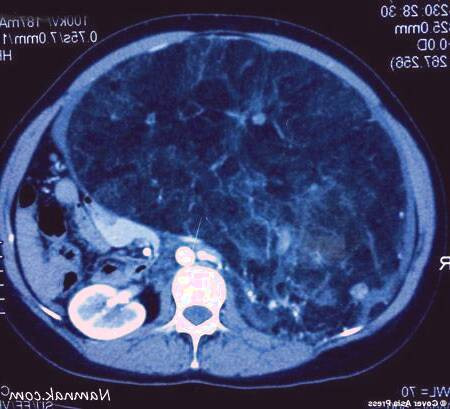

پزشکان با انجام یک عمل جراحی طولانی مدت و پیچیده، به مدت 6 ساعت موفق به برداشتن یک تومور غول پیکر و غیرطبیعی به وزن 7 کیلوگرم از کلیه یک زن هندی شدند. این عمل جراحی دشوار و چالش برانگیز، نیازمند مهارت و تخصص بالای پزشکی بود تا بتوان این تومور انسان را که اندازه آن بسیار غیرمعمول و فراتر از حد طبیعی بود، با موفقیت از بدن بیمار خارج نمود. این دستاورد پزشکی، نشان دهنده پیشرفت های چشمگیر علم پزشکی و جراحی در درمان انواع پیچیده بیماری ها و تومورهای غیرمعمول است.

پزشکان موفق به برداشتن توموری از کلیه زن هندی شدند که بزرگی آن به 7 کیلوگرم رسیده بود. این تومور که در طی دو سال گذشته رشد کرده بود به قدری بزرگ شده که عملکرد کلیه ها را مختل کرده بود. جراحان طی انجام یک عمل جراحی بسیار خطرناک موفق به حذف یک تومور 7 کیلوگرمی از کلیه یک زن شدند. پزشکان با موفقیت تومور بزرگی را از کلیه یک زن هندی خارج کردند که وزن آن به 7 کیلوگرم رسیده بود. این تومور طی دو سال گذشته رشد کرده و عملکرد کلیه ها را مختل کرده بود. جراحان با انجام یک عمل جراحی بسیار پیچیده موفق به برداشتن این تومور 7 کیلوگرمی شدند.

به نقل از دیلی میل، این زن 35 ساله از دهلی نو در هند پس از افزایش بی رویه و بی دلیل وزن و مراجعه به پزشک تحت یک سری از اسکن ها و آزمایشات و سونوگرافی قرار گرفت.

پزشکان پس از انجام آزمایشات مختلف دریافتند که وی دارای توده های خوش خیم در کلیه بوده که این توده ها از عملکرد طبیعی کلیه جلوگیری کرده و در نهایت موجب نارسایی در این اندام شده اند.

اما پس از انجام سونوگرافی و اسکن و آزمایش، پزشکان دریافتند که او دارای angiomyolipoma (یک تومور خوش خیم شایع کلیه که از عروق خونی، عضلات و سلول های چربی تشکیل می شود) است.

پس از بررسی بیشتر آنها دریافتند که این تومور در دو سال گذشته شروع به رشد کرده است.

آنها در نهایت تصمیم به انجام یک عمل جراحی به نام نفرکتومی جزئی گرفتند که یک فرایند برای برداشتن تومور و حفظ بخش سالم اعضای بدن است.

این پزشکان با انجام یک عمل جراحی 6 ساعته موفق به حفظ نیمی از کلیه راست این زن شدند.